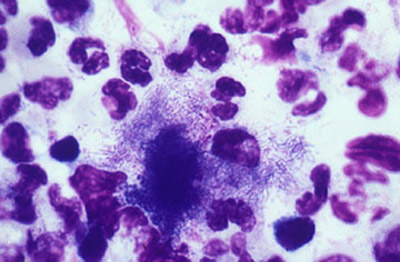

El diagnóstico bacteriológico se puede confirmar por medio de un extendido del material obtenido por expresión canalicular, que demuestre la presencia de las hifas pequeñas y finas del Actynomices , el cual debe ser diferenciado de los hongos verdaderos como la Candida, el Fusarium, y los Aspergilus igualmente causales de esta entidad, aunque con menor frecuencia .